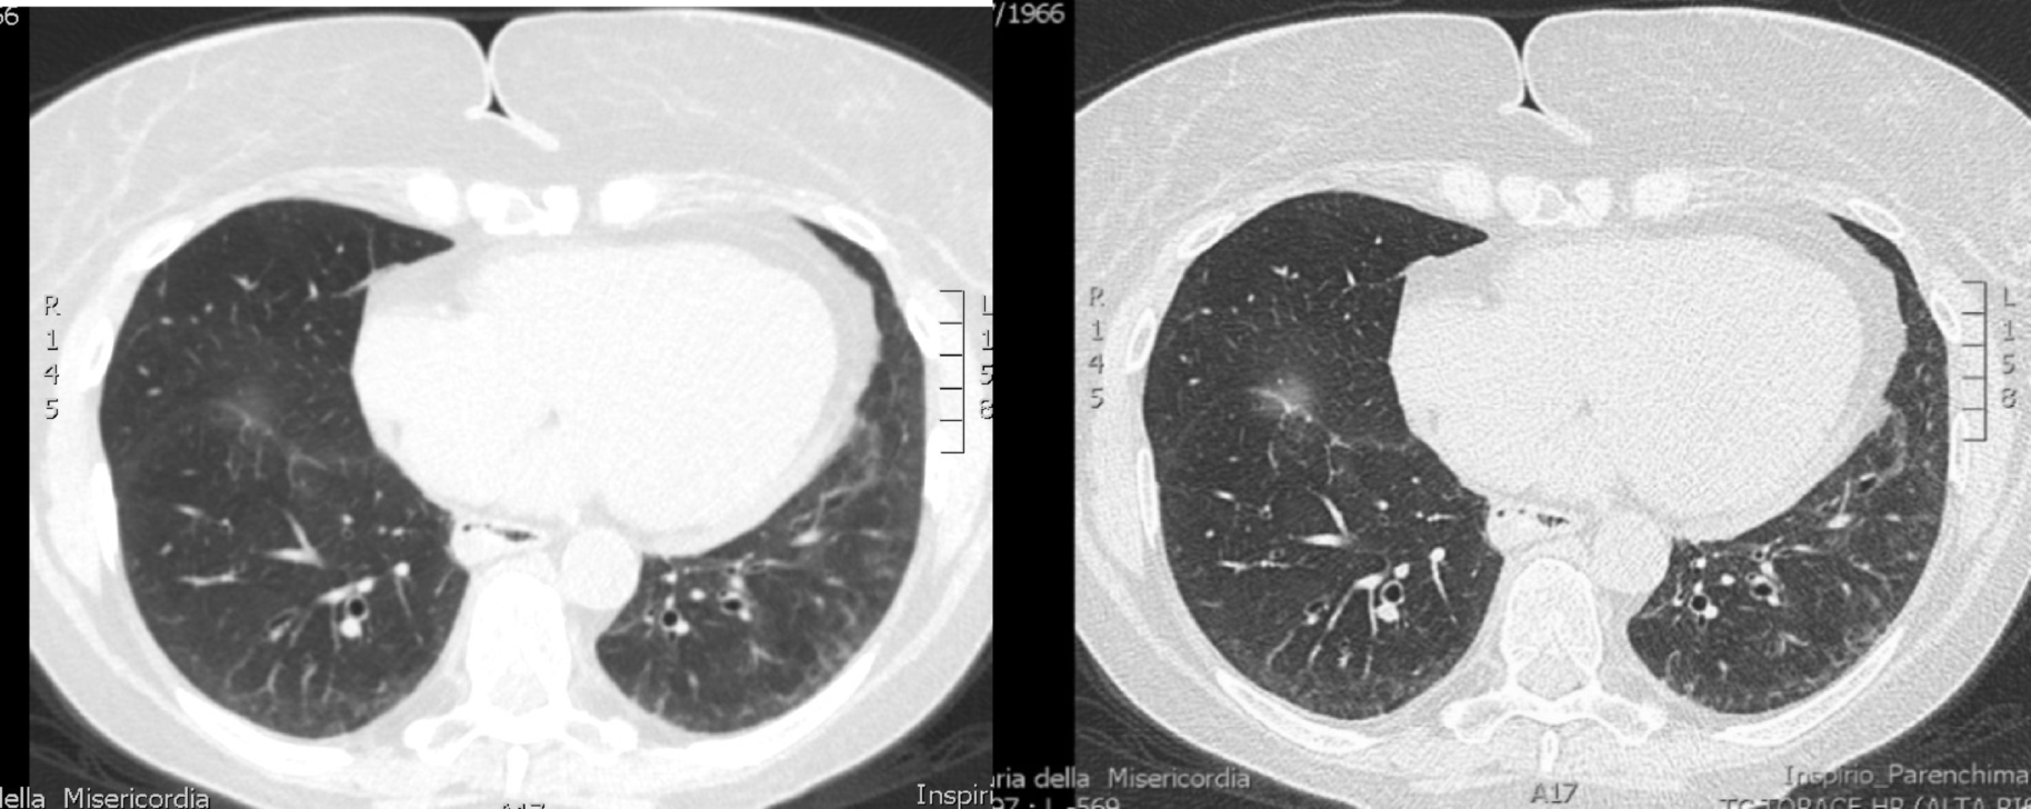

During hospitalisation, the echocardiography showed mild increase in left ventricle (LF) thickness with interventricular septal of 12 mm, not justified by the presence of valvulopathy or systemic arterial hypertension. NT-proBNP was also elevated (1170 pg/ml). Coronary angiography showed no lesions. Serum immunofixation revealed IgM kappa at 6.1 g/L, kappa (κ) light chains at 123 mg/L (normal range: 6–22 mg/L), and lambda (λ) light chains at 53 mg/L (normal range: 5–26 mg/L), with traces of κ light chains on urinary immunofixation. Bone marrow biopsy showed findings consistent with IgM “plasma cell-like” monoclonal gammopathy of undetermined significance (MGUS) without amyloid deposits (Congo red staining and polarized light microscopy were negative). In December 2023, she was admitted again to the cardiology unit due to fatigue, severe dyspnea requiring oxygen supplementation up to 12 L/min, orthostatic hypotension, and elevated troponin levels (1010 ng/L). Echocardiography confirmed mildly increased LV wall thickness with slight of the interventricular septum and preserved EF, with normal filling pressure. High-resolution chest computed tomography (HRCT) showed mosaic attenuation pattern in the middle lobe and lingula, diffuse ground-glass opacities at the bases with interlobular septal thickening and dilated oesophagus (Fig. 1).

Fig. 1

HRCT showing a mosaic attenuation pattern and diffuse ground-glass opacities at the lung bases with interlobular septal thickening

After three months of treatment, the patient reported further improvement in dyspnea and fatigue. Follow-up HRCT showed reduced ground-glass opacities but persistent basal reticular patterns bilaterally (Fig. 3).

Fig. 3

Follow-up HRCT showing a reduction in ground-glass opacities but persistent bilateral basal reticular pattern